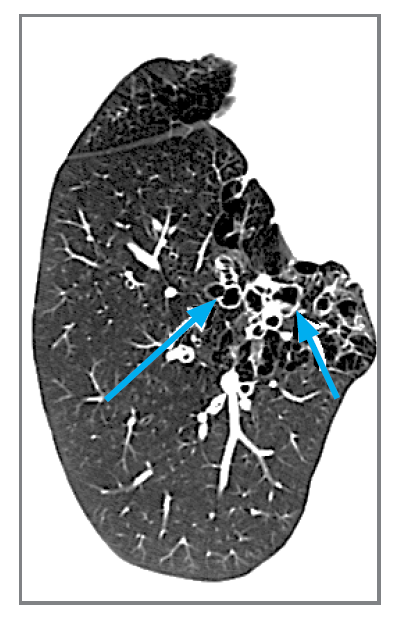

What 2 features are shown here? What condition is this?

traction bronchiectasis and string of pearls. Varicose bronchectasis.